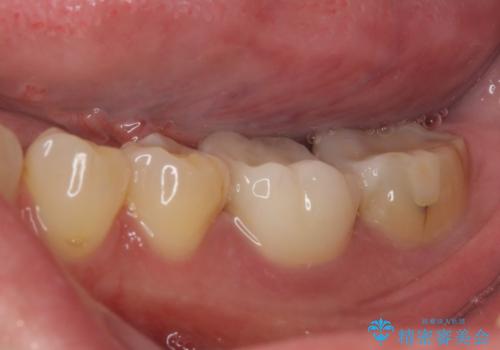

奥歯は虫歯が放置されていましたが、特に症状はなく歯髄の状態も正常でした。

前歯、奥歯ともにオールセラミッククラウンやセラミックインレーにて治療を行うこととしました。

前歯のセラミッククラウンは周りの歯と調和させるためにオーダーメイドタイプのものをおすすめしましたが、元が白すぎていたため、概ね色合いが合えば大丈夫であるとのことで、既製パターンの色調で仕上げました。